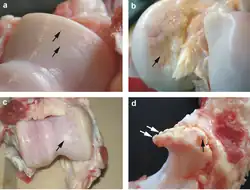

Spektroskopia magnetycznego rezonansu jądrowego stawu kolanowego wykazuje zmiany zwyrodnieniowe tego stawu |

a. erozję chrząstki

b. zmiany nadżerkowe chrząstki

c. procesy naprawcze chrząstki

d. osteofit kości łokciowej